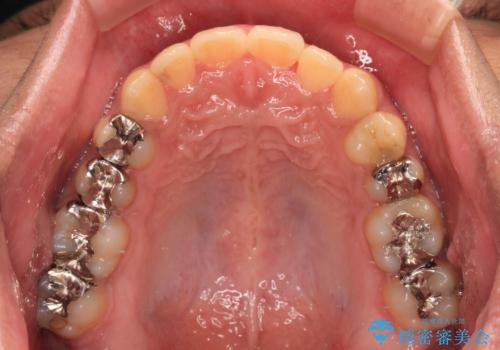

前歯のクロスバイト インビザラインによる矯正治療

- 上下のクロスバイトと前歯のデコボコを気にして来院された患者様です。

インビザラインを用い、IPR(歯と歯の間を削る)と歯列全体を拡大させることで、歯並びを整えていくこととしました。

インビザライン特有の、治療後半に奥歯が咬み合わないという事象が長引きました。

咬み合わないときの対処方法は色々とありますが、ゴムかけなどを活用して噛めるようにしました。